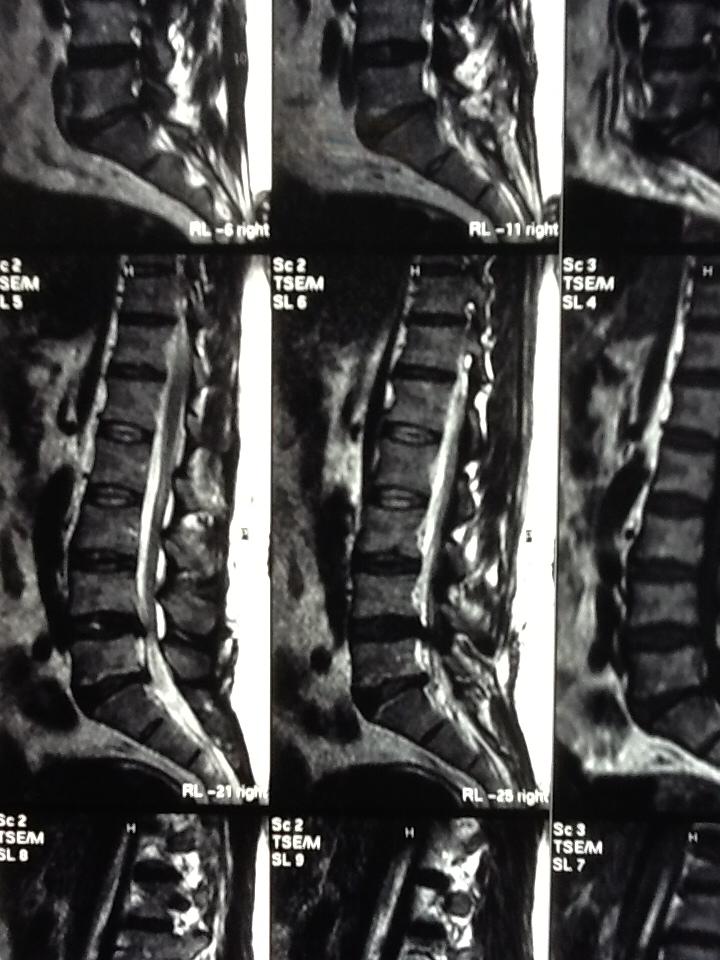

آندوسکوپی دیسک ال4 ال5

دکتر شهنام بابلی

عکس ام آر آی